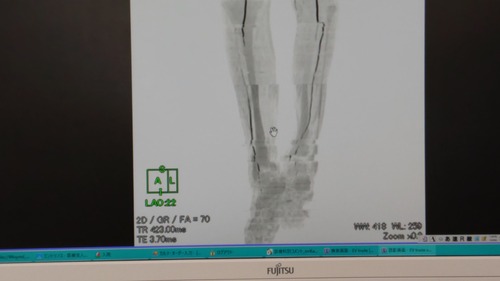

レントゲンの写真(医師の許可あり)

この画像は足の後ろだと思いますが、

前からの画像は、ほぼ、血管は真っ白な状態でした